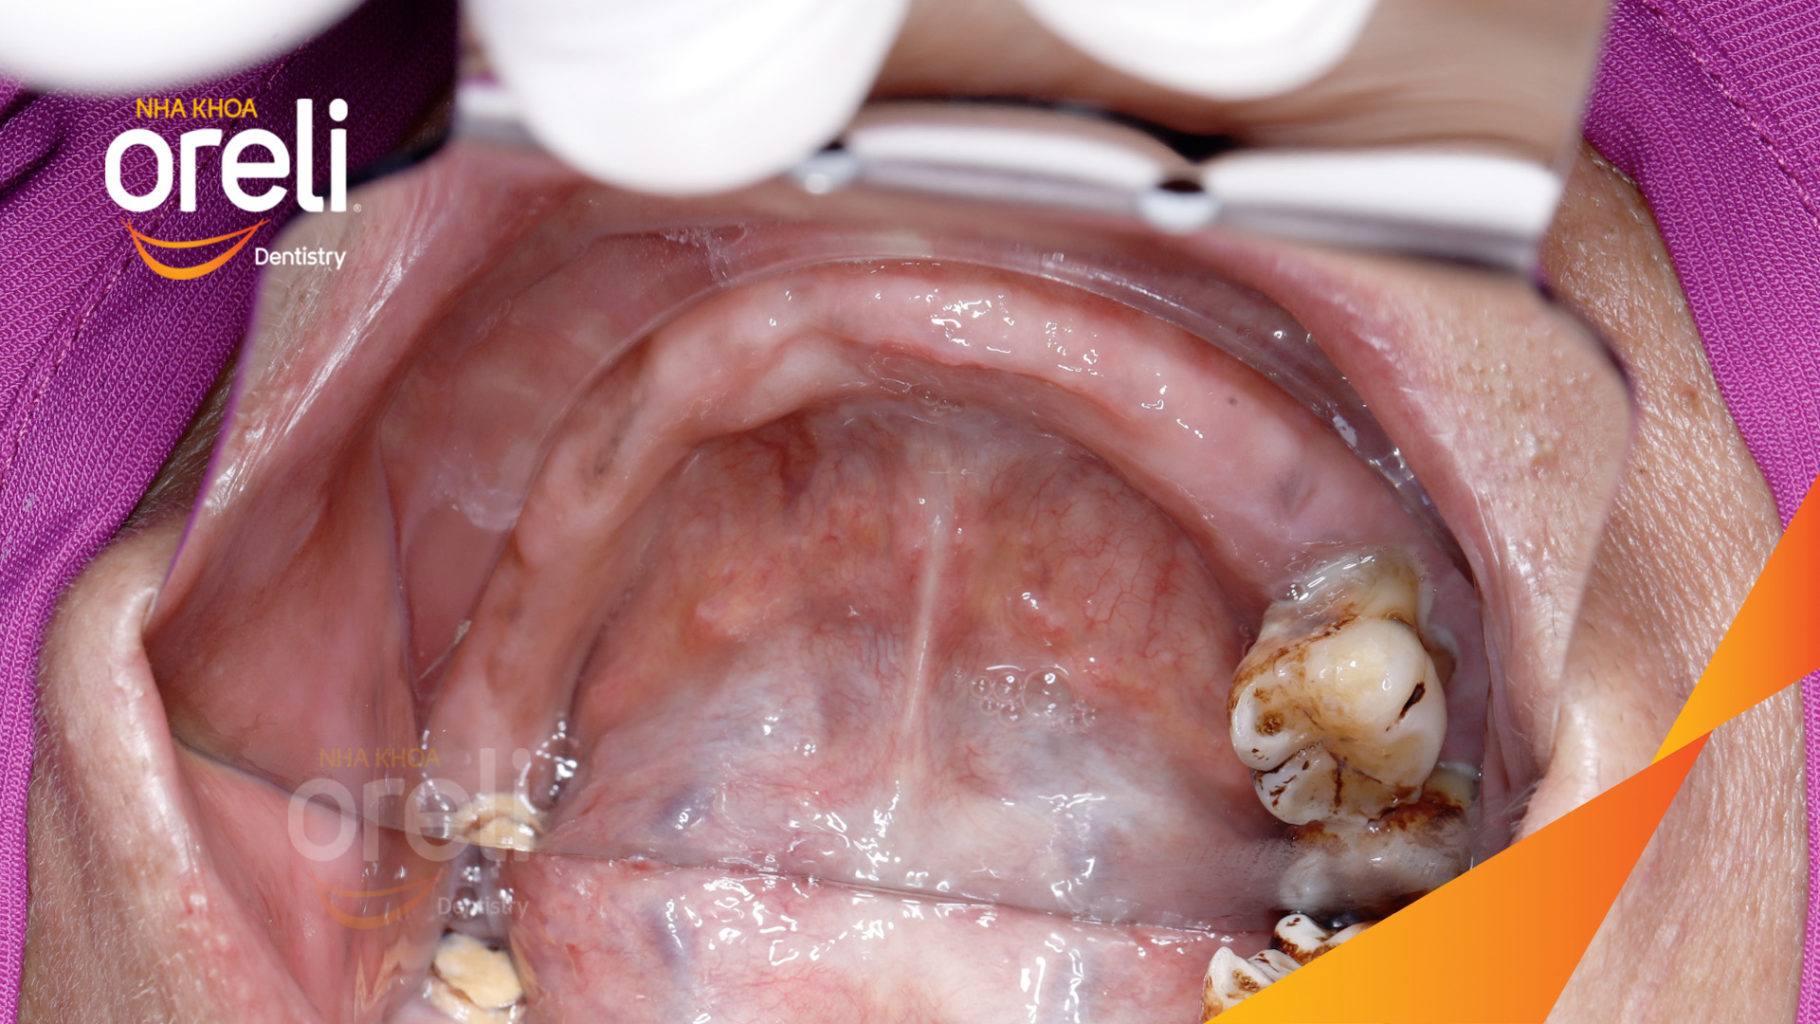

Sáu trụ Implant hàm dưới được đặt xong

Xương sống hàm tiêu và mất nhiều răng